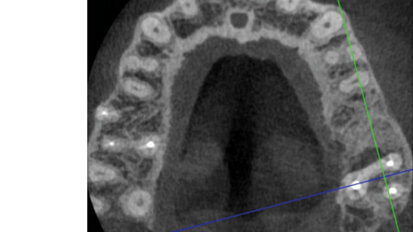

Nový úsměv za jeden den

Čt. 28. května 2020